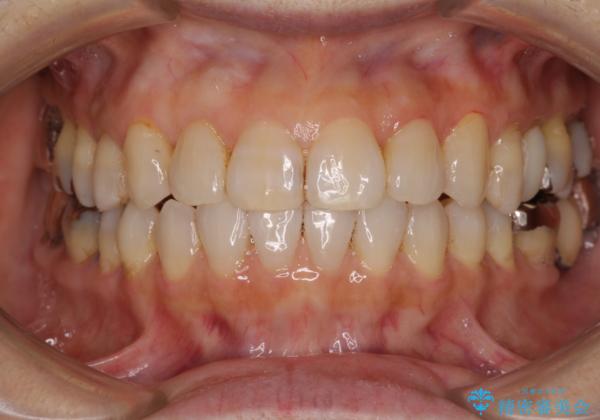

前歯の突出感と上下の隙間 インビザラインによる矯正治療

- 前歯の上下スペースと前歯の隙間を気にして来院された患者様です。

インビザラインにより上下の前歯の隙間を閉じながら、IPRを用いて口元の突出感を合わせて改善していくこととしました。

上下の隙間に舌が入り込むことが、すきっ歯やオープンバイトの原因であったため、舌の筋肉のトレーニングも並行して行い、後戻りの抑制を図りました。